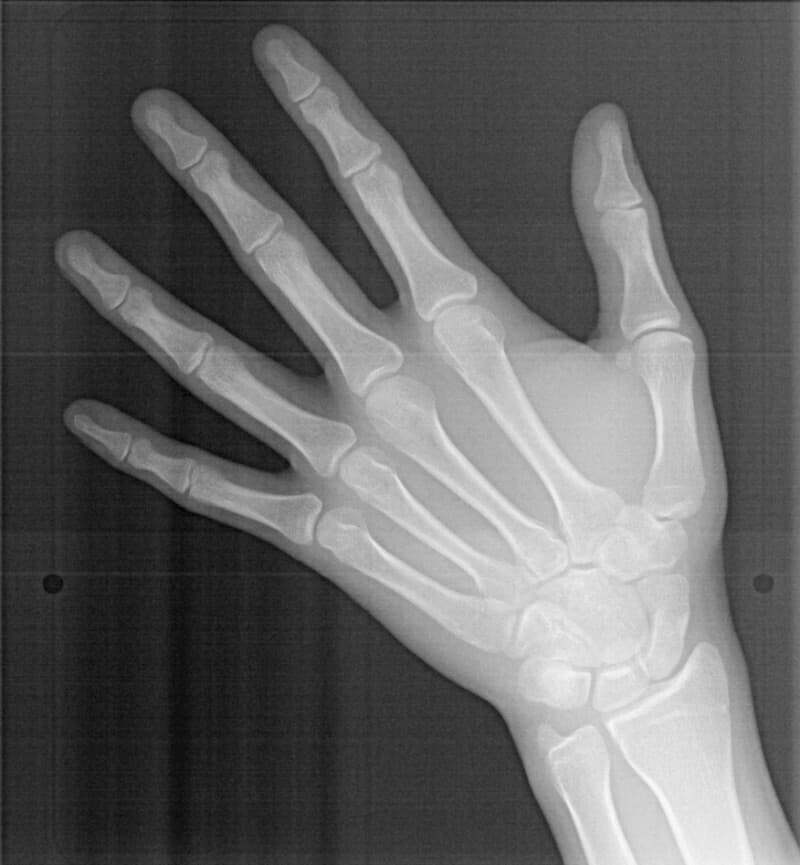

手根骨レントゲン分析結果:

口腔内やセファロ分析とは違い、今後の下顎の旺盛なgrowth(成長)を示唆しない像です。家族歴から考えても、極端に高身長ではないと予測されるので、将来外科矯正ケースになるリスクは実はさほど高くないと考えました。

セサモイドボーンも認められ、家族歴からも、今後の旺盛な下顎の成長の恐れがないと思われる所見です。